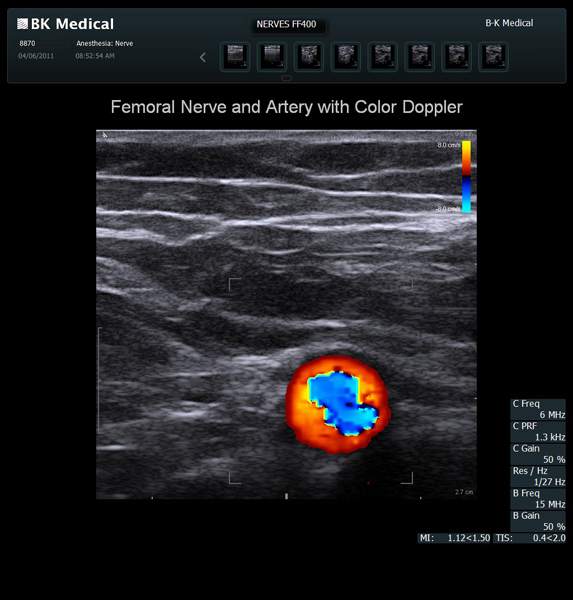

The Flex Focus 400 exp ultrasound system offers premium image quality with fast frame rates for excellent temporal resolution. The system features Automatic Mode Adjustment (AMA) to optimize high resolution B-Mode Imaging when changing modes and depth.

Transducers Designed for Guidance

BK Medical offers high-frequency linear transducers, imaging from 18-2 MHz for upper and lower extremities, and curved array abdominal transducer 8820e for special deep nerves or paravertebral/spinal applications. Our transducers provide superb detail that makes it easy to see your needle during procedures.